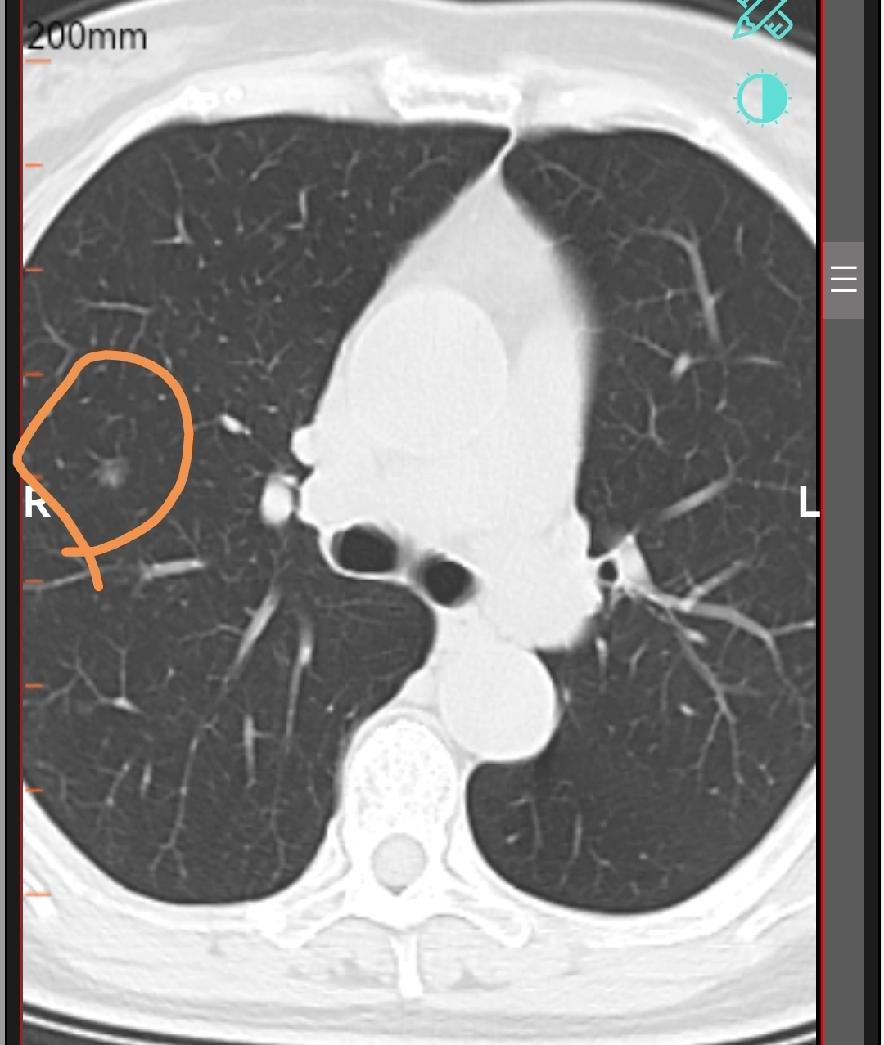

肺部结节有一部分是恶性的,这一小部分恶性结节导致每一个结节患者都很焦虑,肺结节如

肺部结节若为肺癌,会有这些“危险变化” 在临床诊疗中,肺部结节是呼吸科常见的“信

肺部结节多数是良性,为什么还有很多人害怕,问题出在少数当中 肺部结节是很多人的噩